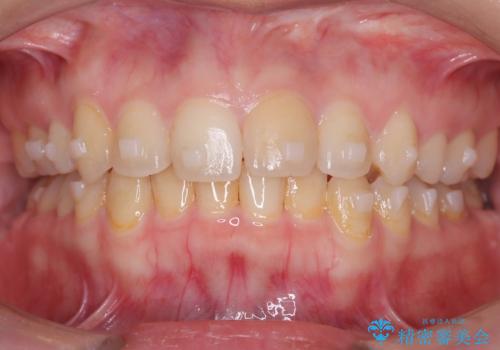

矯正後の後戻り インビザラインで改善

- 前歯のガタツキが気になると来院されました。

マウスピース矯正治療を選択しました。

前歯のガタツキを改善する治療法として、マウスピース矯正が適していることが多いです。

マウスピース矯正は、金属製のブラケットやワイヤーを使用せずに、透明なマウスピースを装着して歯を移動させる方法です。そのため、目立たず、痛みも少ないです。